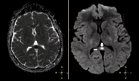

Se realizó ecografía ocular que mostró opacidades vítreas severas con formación de membranas densas en cuadrantes inferiores y desprendimiento vítreo posterior con tracción inferior. Se practicó vitrectomía con toma de muestras para PCR, que resultó positiva para virus Epstein-Barr (EBV) a partir del ciclo 31.4, mientras que fue negativa para otros virus como CMV, herpes y toxoplasma. Los análisis sanguíneos descartaron inmunodeficiencias u otras condiciones asociadas.

Mostró opacidad de medios en ojo derecho, disco óptico mal definido, proliferación fibrovascular en área del disco óptico y zona inferior, además de hiperfluorescencia del disco óptico que aumentaba con el tiempo del tránsito angiográfico. Estos hallazgos sugirieron vasculitis viral con neovascularización secundaria y posible edema macular difuso.